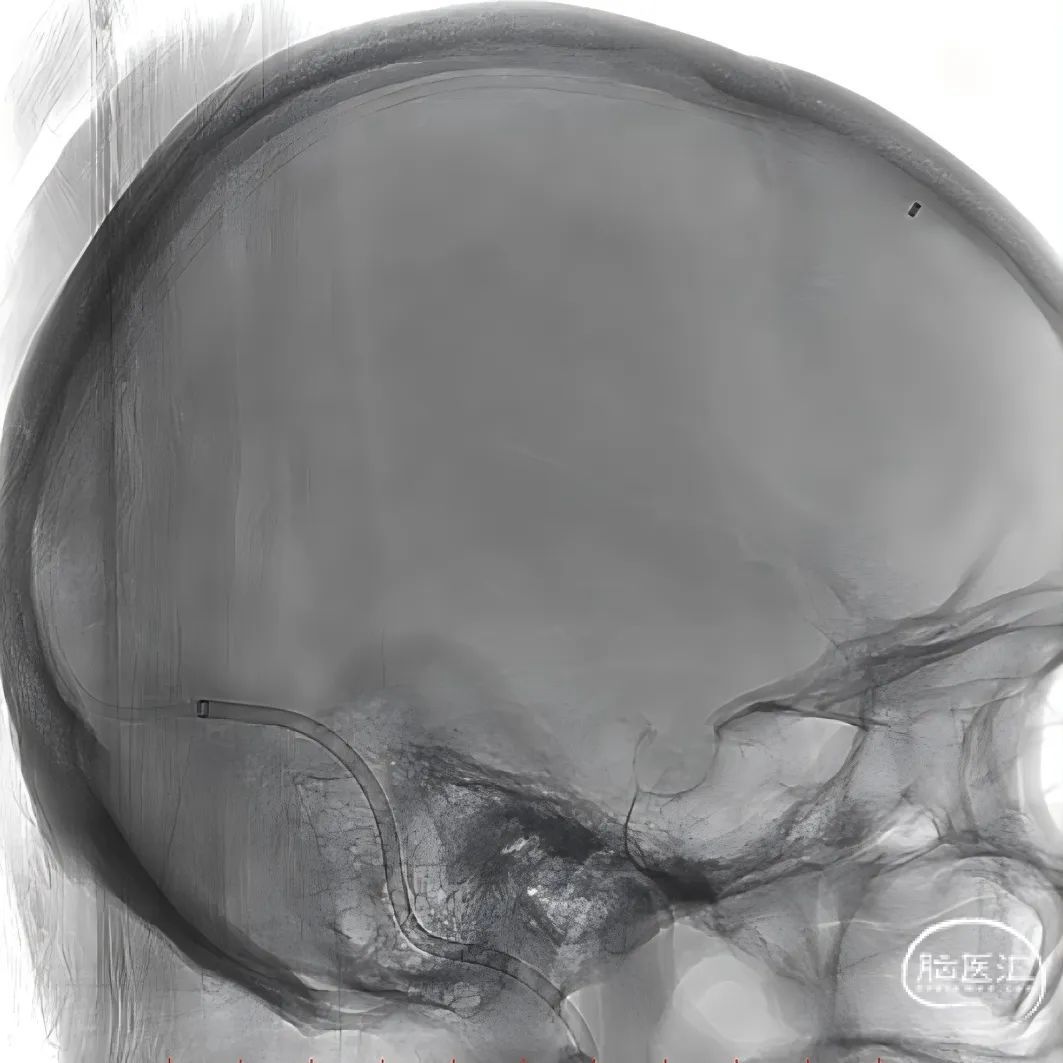

股动脉穿刺置5F鞘做静脉窦造影,股静脉穿刺置8F鞘进行治疗。260cm泥鳅导丝,将132cm 0.068" React™导管送至上矢状窦前部,尽量推高长鞘,增加支撑力。

经中间管手推造影,确认血栓位置。